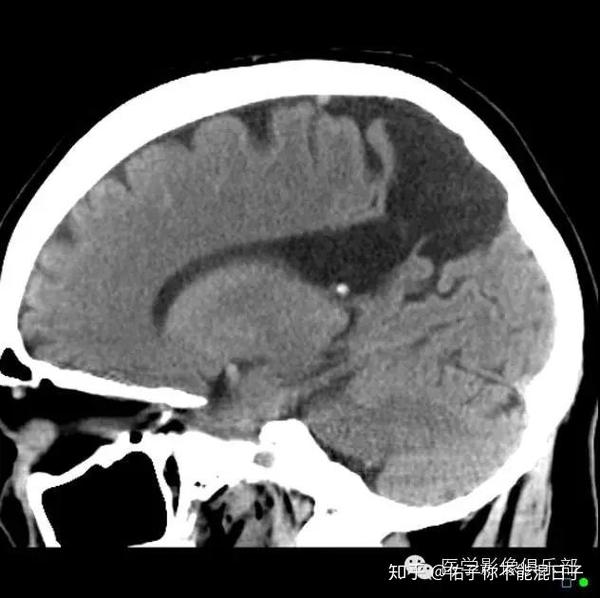

脑灰质异位影像诊断

精品课件| 脑灰质异位症的影像诊断

脑灰质异位ct图片

脑白质和脑灰质ct图片